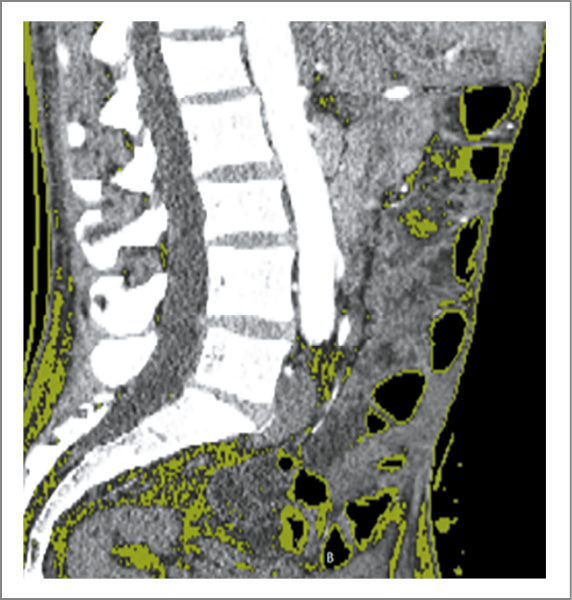

В план операции входило устранение колостомы и наложение десцендо-сигмоанастомоза. Факторы риска развития операционных осложнений: мужской пол, курение, саркопения, нутритивный дефицит, длительность оперативного вмешательства, выраженный спаечный процесс. Для минимизации риска несостоятельности швов анастомоза произведена оценка выраженности саркопении. Оценка состава тела производилась путем сегментации изображений в сагиттальном срезе на уровне LIII-позвонка, полученном по данным КТ.

Рис. 3. Послойное изображение (кожа, кишка).

Перед планированием операции произвели оценку морфологического и физиологического состояния кишечника, а также оценили особенности и распространенность спаечного процесса. Для этого выполнили КТ с внутривенным и пероральным контрастированием с последующей сегментацией изображений и 3D-реконструкцией с использованием набора программных инструментов SliceOmatic, OsiriX, InVesalius. Пероральное контрастирование с отсроченной КТ подтвердило отсутствие обструкций и нарушений пассажа контрастного препарата по кишечнику. Таким образом, доказана нецелесообразность выполнения тотального адгезиолизиса, что уменьшало травматичность и длительность планируемой операции.

Рис. 4. Участки кишки, максимально припаянные к передней брюшной стенке.

Методику выполнения хирургического доступа и его локализацию, учитывая распространенность спаечного процесса, рассчитали с помощью 3D-моделирования сегментированного изображения (рис. 2–4). В автоматическом режиме выделены пиксели плотностью от -226 HU до 3071 HU, что соответствовало рентгенплотности кожи и подкожной клетчатки. Проведенное исследование позволило выделить зоны адгезии толстой и тонкой кишки к брюшной стенке, представляющие повышенную опасность для выполнения доступа.